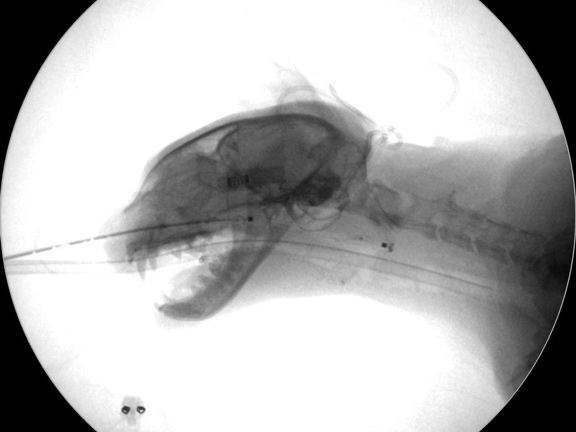

カテーテルを挿入した様子

バルーン用のガイドワイヤー